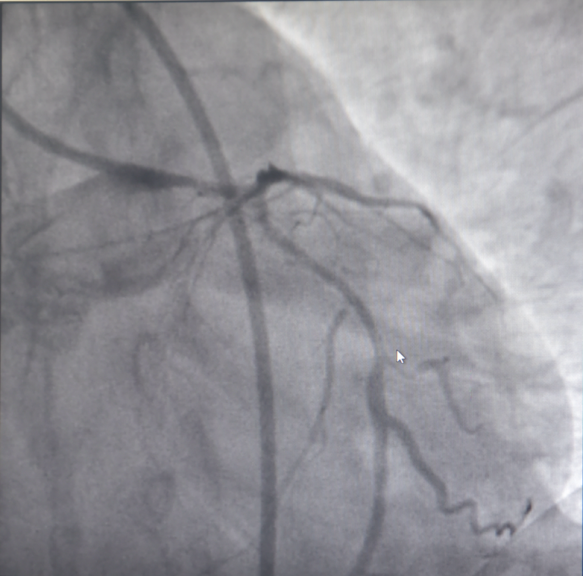

随后,患者立即被送往导管室,揭主任携副主任医师蒋溢为迅速给患者完成了冠脉造影,术中见患者左主干明显变窄,回旋支闭塞,血流TIMI0级,前降支次全闭塞,血流TIMI1级。但此时尚未能明确患者是否为冠脉痉挛或冠脉自发夹层,揭英纯和蒋溢为副主任医师当机立断,为患者快速完成了血管内超声检查,原来是冠状动脉自发夹层!考虑到患者冠脉已经闭塞,遂在IVUS指导下选择切割球囊精准对闭塞血管进行切割扩张,恢复回旋支及前降支正常血流。

左主干至回旋支、前降支自发性冠状动脉夹层、血肿压迫真腔

血管再通,血流恢复正常